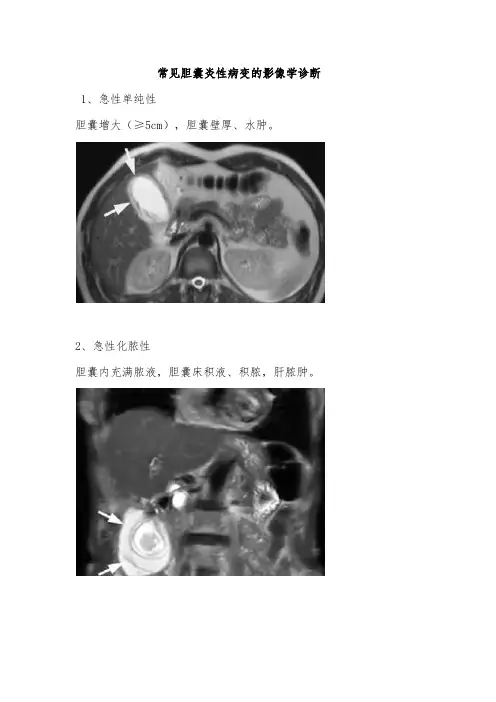

常见胆囊炎性病变的影像学诊断 1、急性单纯性

胆囊增大(≥5cm),胆囊壁厚、水肿。

2、急性化脓性

胆囊内充满脓液,胆囊床积液、积脓,肝脓肿。